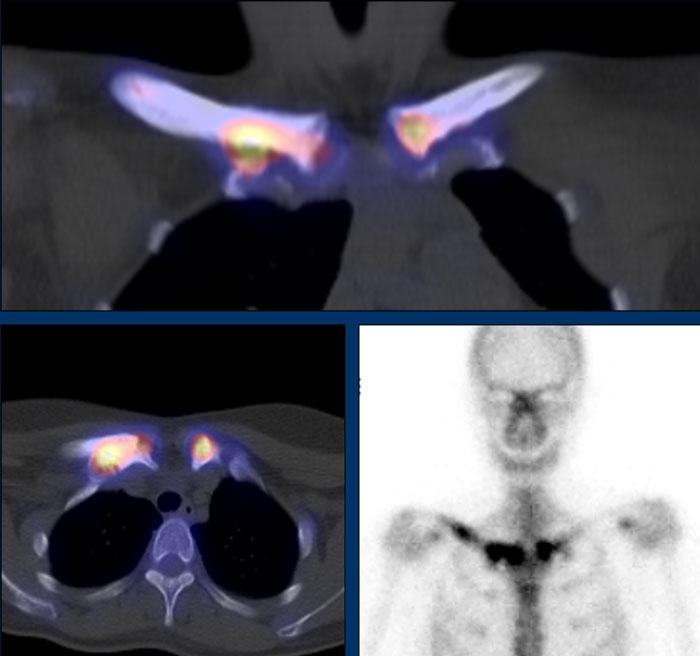

Dày vỏ xương, xơ cứng và phì đại xương ở thân xương và hành xương đòn phải, cũng như hành xương đòn trái.

SPECT-CT và xạ hình xương của cùng một bệnh nhân. Ghi nhận tăng hấp thu chất đánh dấu phóng xạ bất thường tại các vùng tương ứng, phản ánh tình trạng tăng chu chuyển xương.